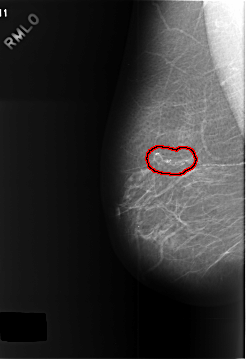

C_0392_1.RIGHT_MLO

RIGHT_MLO LINES 5744 PIXELS_PER_LINE 3992 BITS_PER_PIXEL 12 RESOLUTION 50 OVERLAY

FILE: C_0392_1.RIGHT_MLO.OVERLAY

TOTAL_ABNORMALITIES 1

ABNORMALITY 1

LESION_TYPE CALCIFICATION TYPE PLEOMORPHIC DISTRIBUTION SEGMENTAL

ASSESSMENT 4

SUBTLETY 5

PATHOLOGY BENIGN

TOTAL_OUTLINES 1

BOUNDARY